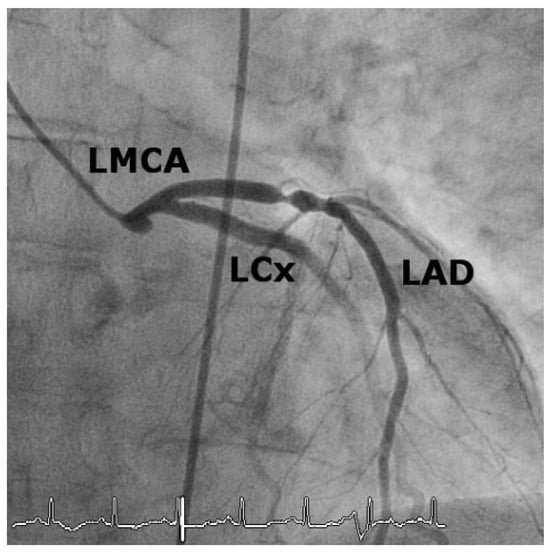

Iatrogenic Left Main Stem Stenosis After Surgical Aortic Valve Replacement

by Jens Robert, David Tüller and Stephan Windecker

Cardiovasc. Med. 2011, 14(3), 101; https://doi.org/10.4414/cvm.2011.01578 - 23 Mar 2011

Surgical aortic valve replacement (SAVR) represents the gold standard in the treatment of symptomatic severe aortic valve stenosis as reflected by the class I indication assigned in the ACC/AHA and ESC guidelines. SAVR effectively relieves symptoms, improves quality of life as well as [...] Read more.

Surgical aortic valve replacement (SAVR) represents the gold standard in the treatment of symptomatic severe aortic valve stenosis as reflected by the class I indication assigned in the ACC/AHA and ESC guidelines. SAVR effectively relieves symptoms, improves quality of life as well as prognosis of affected patients. As with any therapeutic intervention, SAVR is associated with some short and long term adverse events including death, stroke, myocardial infarction, renal failure, bleeding, as well as structural and non-structural valve deterioration. We present two cases of iatrogenic left main stemstenosis within less than one year after SAVR, describe the management and discuss the literature. Full article